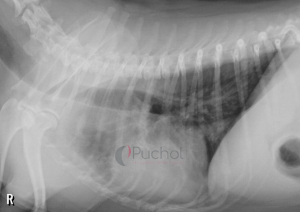

La hipertensión pulmonar en perros es un hallazgo patológico generalmente infradiagnosticado en la clínica de pequeños animales, que consiste en el incremento de la presión arterial, sistólica o diastólica, a nivel de la circulación pulmonar. Su aparición se puede deber a múltiples causas, la mayoría de ellas relacionadas con alteraciones cardiacas o pulmonares.

Las síntomas de la hipertensión pulmonar en perros pueden ser variable, pero generalmente incluyen tos, intolerancia al ejercicio, disnea (dificultad respiratoria), cianosis (coloración azulada de las mucosas), sincope (sonidos de vómitos y pérdida de consciencia), entre otros.

La hipertensión pulmonar en perros puede deber a una variedad de causas, la mayoría de ellas relacionadas con alteraciones cardiacas o pulmonares. Entre las causas más comunes se encuentran: